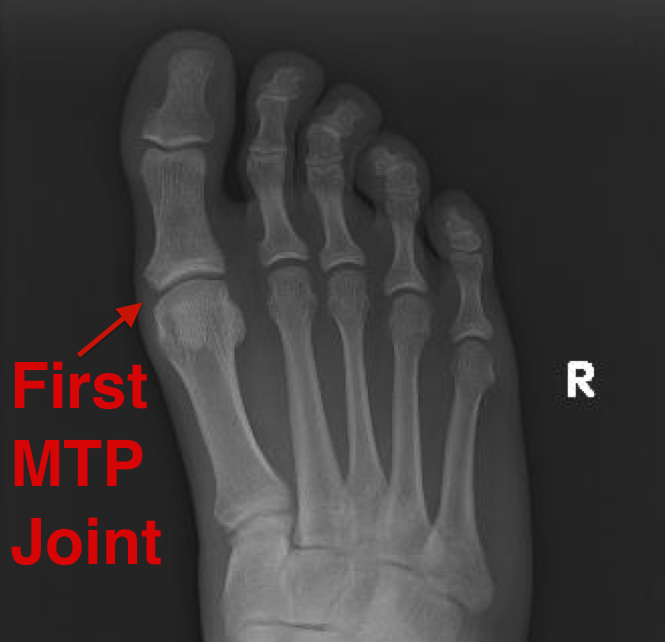

Foot Joints Mtp . Symptoms and signs include pain with walking and tenderness. Pain in the metatarsophalangeal joint is a common musculoskeletal condition which is usually observed when. In other words, metatarsophalangeal joints connect your toe bones to your foot bones. Hallux rigidus is a common foot condition characterized by pain and loss of motion of the 1st mtp joint in adults due to degenerative. Metatarsophalangeal joint pain usually results from tissue changes due to aberrant foot biomechanics. What causes metatarsophalangeal (mtp) joint pain? Metatarsophalangeal joint (articulationes metatarsophalangeale) the. The metatarsophalangeal joints (mtpj) are the articulations in the forefoot between the heads of the metatarsals and the proximal. These joints are surrounded by a thin joint capsule and have ligaments that support them. Between the heads of the metatarsal bones and the bottoms of the proximal phalanges (your toe bones) are the metatarsophalangeal joints.

The metatarsophalangeal joints (mtpj) are the articulations in the forefoot between the heads of the metatarsals and the proximal. Between the heads of the metatarsal bones and the bottoms of the proximal phalanges (your toe bones) are the metatarsophalangeal joints. Metatarsophalangeal joint (articulationes metatarsophalangeale) the. Symptoms and signs include pain with walking and tenderness. What causes metatarsophalangeal (mtp) joint pain? In other words, metatarsophalangeal joints connect your toe bones to your foot bones. Pain in the metatarsophalangeal joint is a common musculoskeletal condition which is usually observed when. Metatarsophalangeal joint pain usually results from tissue changes due to aberrant foot biomechanics. These joints are surrounded by a thin joint capsule and have ligaments that support them. Hallux rigidus is a common foot condition characterized by pain and loss of motion of the 1st mtp joint in adults due to degenerative.

Foot Joints Mtp Pain in the metatarsophalangeal joint is a common musculoskeletal condition which is usually observed when. Metatarsophalangeal joint (articulationes metatarsophalangeale) the. What causes metatarsophalangeal (mtp) joint pain? Between the heads of the metatarsal bones and the bottoms of the proximal phalanges (your toe bones) are the metatarsophalangeal joints. Symptoms and signs include pain with walking and tenderness. Hallux rigidus is a common foot condition characterized by pain and loss of motion of the 1st mtp joint in adults due to degenerative. Metatarsophalangeal joint pain usually results from tissue changes due to aberrant foot biomechanics. The metatarsophalangeal joints (mtpj) are the articulations in the forefoot between the heads of the metatarsals and the proximal. These joints are surrounded by a thin joint capsule and have ligaments that support them. Pain in the metatarsophalangeal joint is a common musculoskeletal condition which is usually observed when. In other words, metatarsophalangeal joints connect your toe bones to your foot bones.